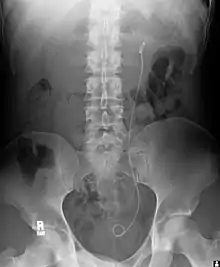

| Ureteral stents are used to ensure the patency of a ureter, which may be compromised, for example, by a kidney stone. This method is sometimes used as a temporary measure to prevent damage to a blocked kidney until a procedure to remove the stone can be performed. | ![]() Example of a ureteral stent used to alleviate hydronephrosis of the kidney |